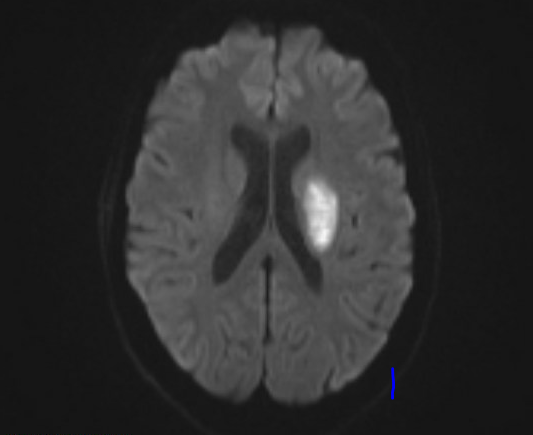

55-year-old female was admitted to our inpatient unit for neurological rehabilitation following stroke. Examination revealed right sided hemiparesis with power of 0/5 in upper limb and 2/5 in lower limb. Laboratory investigations were normal. Her lipid profile was raised. She also had an unremarkable 24-hour electrocardiogram and carotid Doppler. Brain Computed tomography and MRI scans showed left basal ganglia infarct. She was treated as an acute ischaemic stroke and commenced on rehabilitation. She was transferred to our unit to continue her neurological rehabilitation which was progressing slowly (Figure 1a –1c­­).

Figure 1c Magnetic resonance imaging showing area of left basal ganglia infarct.